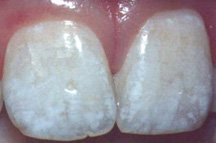

Ампициллин может провоцировать флюороз

Ампициллин может провоцировать флюорозВ октябрьском номере журнала of Pediatric & Adolescent Medicine сообщается, что амоксициллин может привести к поражениям эмали зубов (флюорозу) у детей. Флюороз - один из самых частых дефектов развития зубной эмали, который связан с воздействием избыточного количества фторидов. При флюорозе отмечаются структурные изменения и деминерализация зубной эмали. Проявления флюроза варьируют от небольших пятен до безобразных сливающихся рытвин и отвратительных изменений цвета зубов. Ученые наблюдали детей в возрасте от 0 до 32 месяцев жизни. Употребление амоксициллина каждые 3-4 месяца увеличивал относительный риск поражения резцов верхней челюсти флюрозом более чем в два раза. По мнению доктора стоматологии из университета Огайо С. Пол, необходимы дальнейшие исследования данного феномена на экспериментальной модели . Проведение исследования поддержал Национальный институт здоровья США.